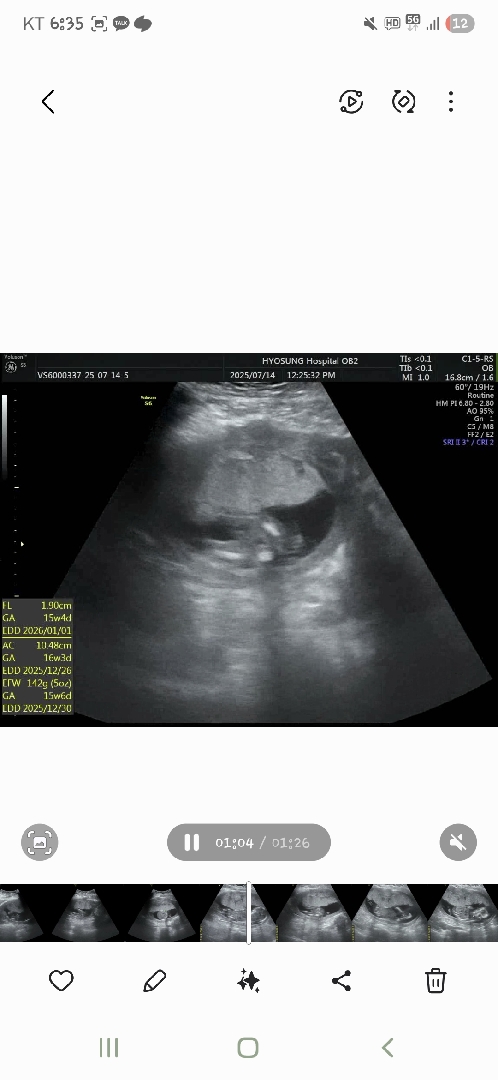

딸일까요??아들일까요???

자세때메 정확치않다구 원장님이 말씀하시는데 성별이 멀까요???

너무 흐려서모르겠지만 ㅠ 가운데 뭔가 있는거같기두해유